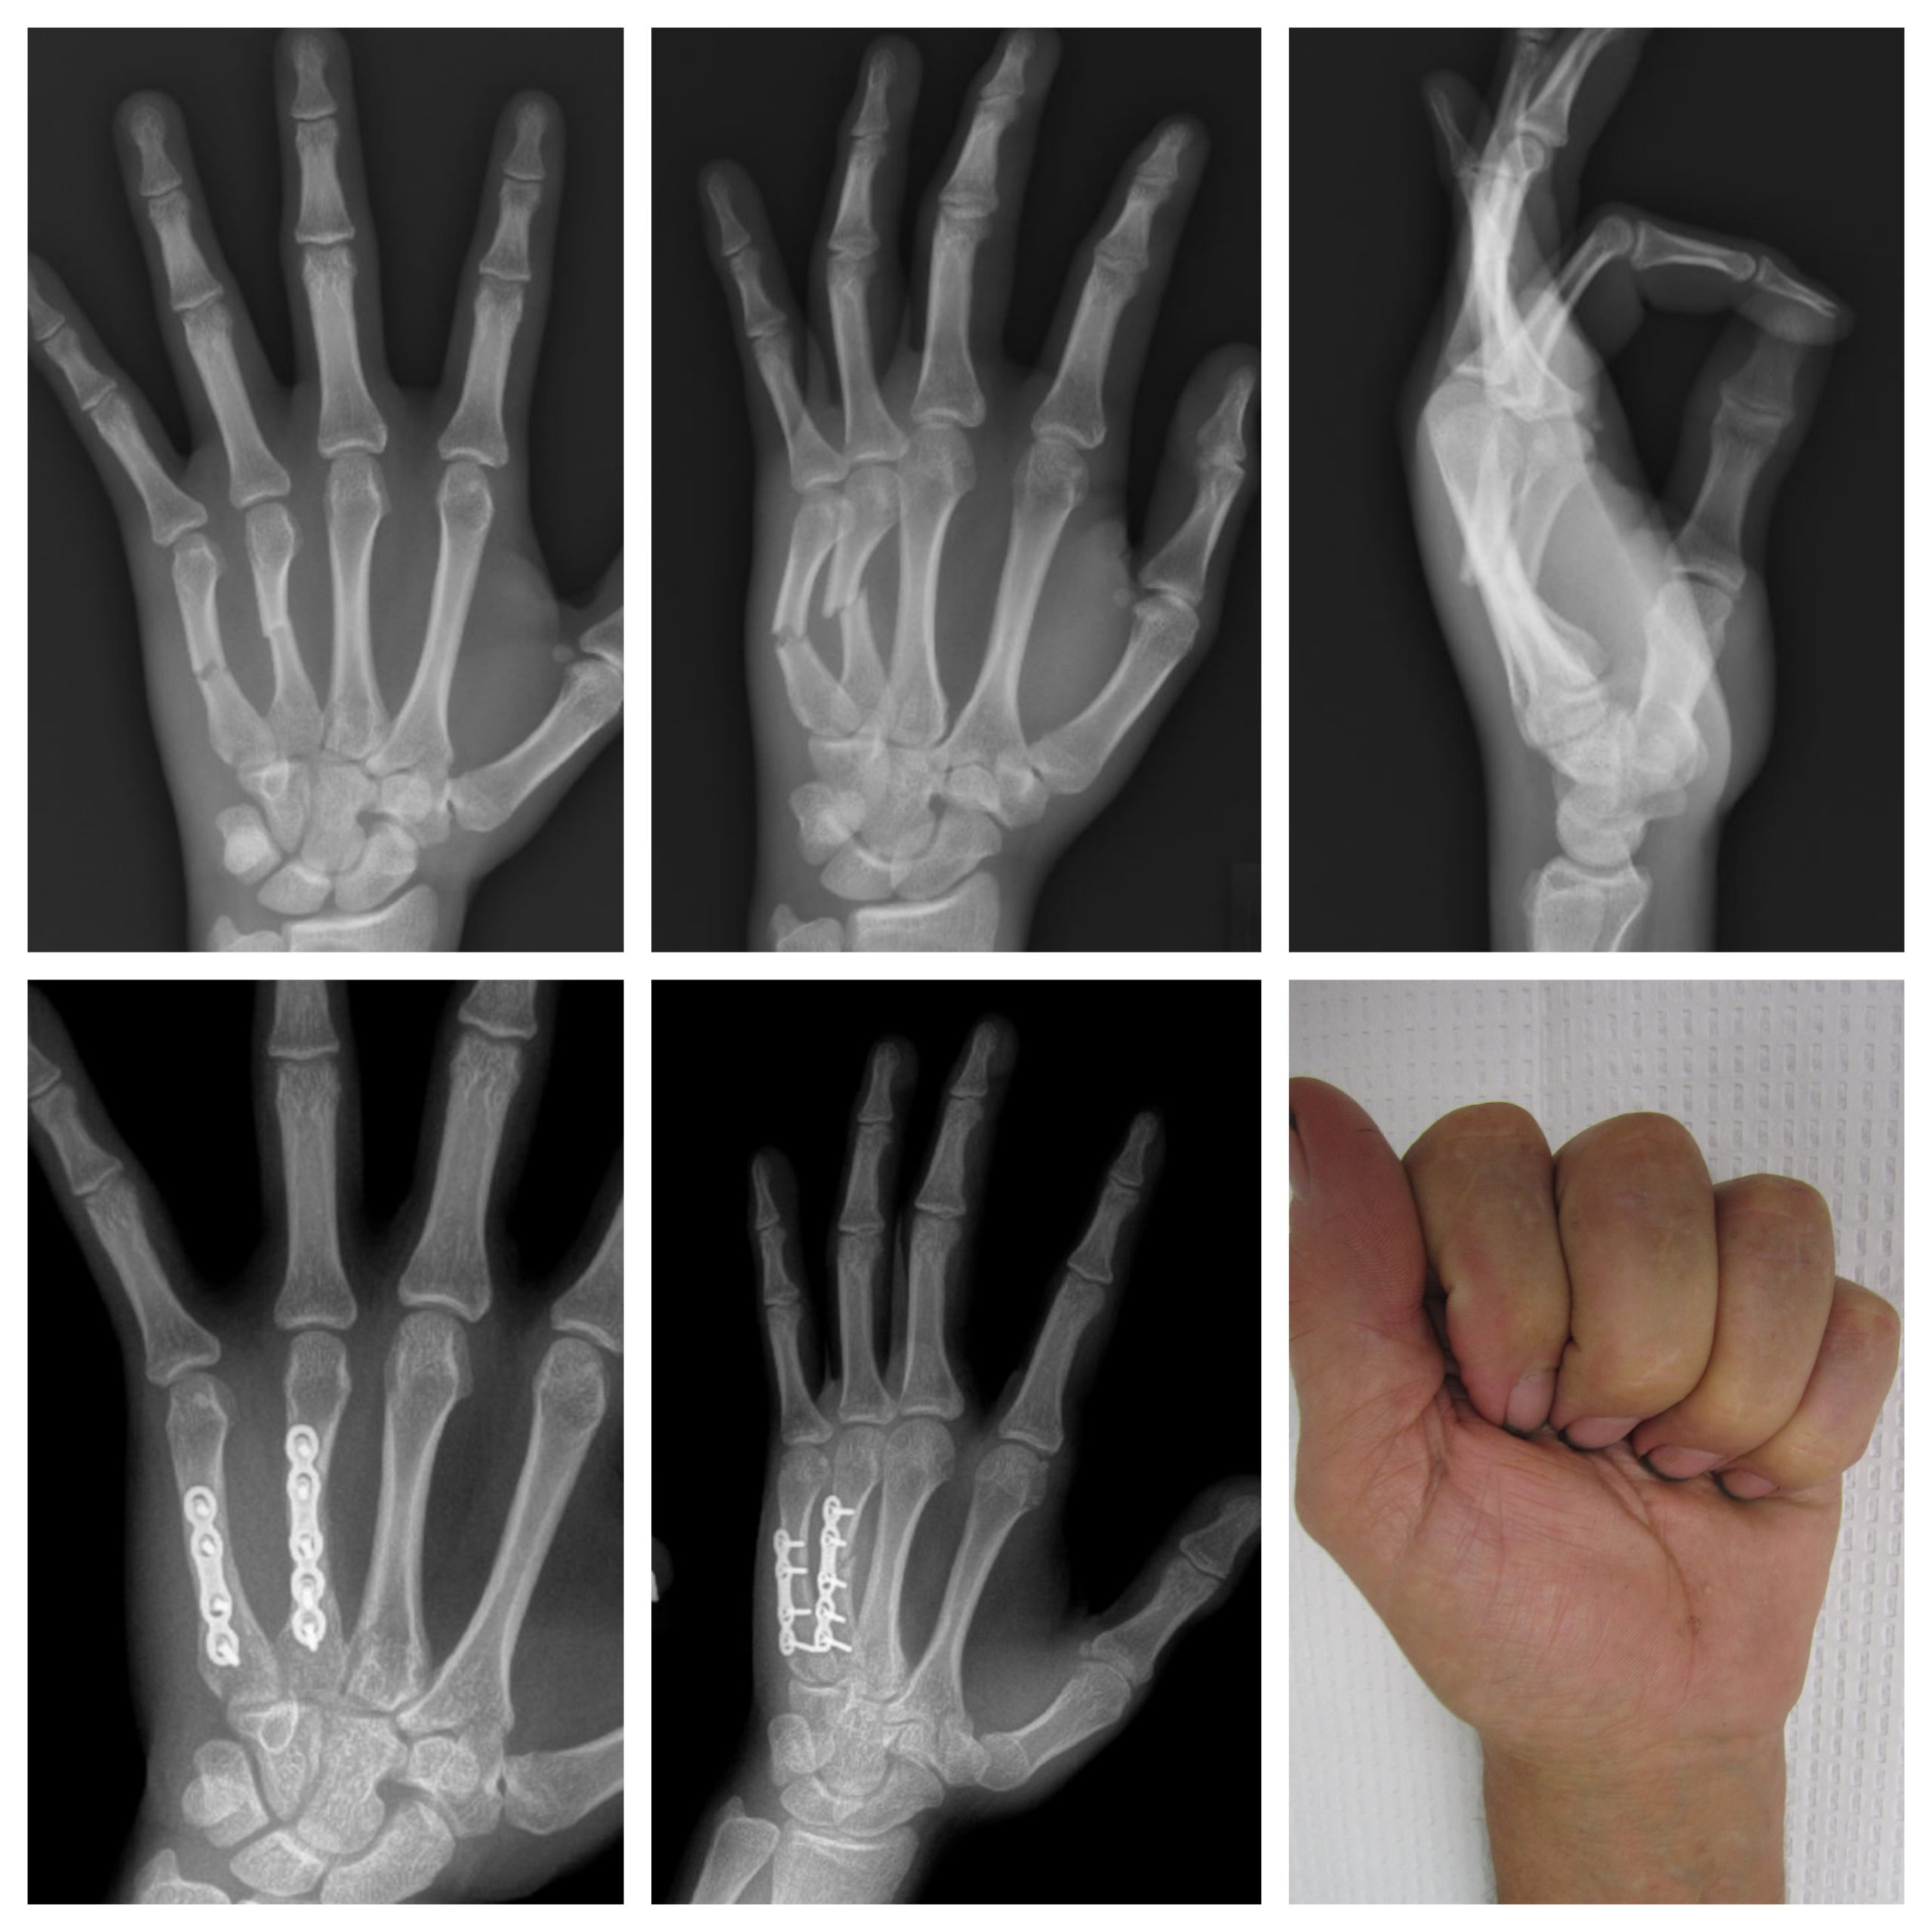

X-rays:

Images below are from a patient with 4th and 5th metacarpal shaft fractures in the hand. The fractures were displaced and unstable, requiring surgery to improve the patient’s hand function. ORIF with plates and screws was performed.